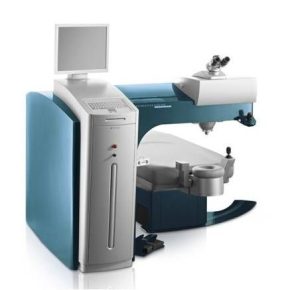

4) Como é feito o implante do Anel de Ferrara?

Dr. Gustavo Bonfadini, explica que é aplicada anestesia local por meio de colírio, sem necessidade de internação. Atualmente este procedimento é idealmente realizado por meio de um Laser de Femtosegundo. Com o uso do Laser, não há corte com bisturi, fazendo com que a incisão seja criada a partir de uma fotodisrupção (separação) das lamelas da córnea, confeccionando assim um túnel no interior da Córnea. Exatamente conforme planejado pelo cirurgião especialista em córnea, conferindo uma maior previsibilidade e eficiência no implante do anel.

5) Quais as vantagens do implante do Anel de Ferrara com uso do Laser de Femtosegundo ?

Dr. Gustavo Bonfadini, relata que no implante do Anel de Ferrara com uso do Laser de Femtosegundo, as incisões e o túnel para implante dos anéis intracorneanos podem ser moldados e posicionados com um elevado grau de precisão:

Trajetórias pré-programadas para todos os segmentos de anel;

Opção para personalização da trajetória;

Dois túneis diferentes na córnea;

Duas diferentes profundidades na córnea;

Possibilidade de um ou dois túneis na córnea;

Dois túneis separados ou um anel completo de 360°;

Duas opções de corte na vertical (cut on /off) na córnea;

Fácil inserção do anel graças à confecção completa.